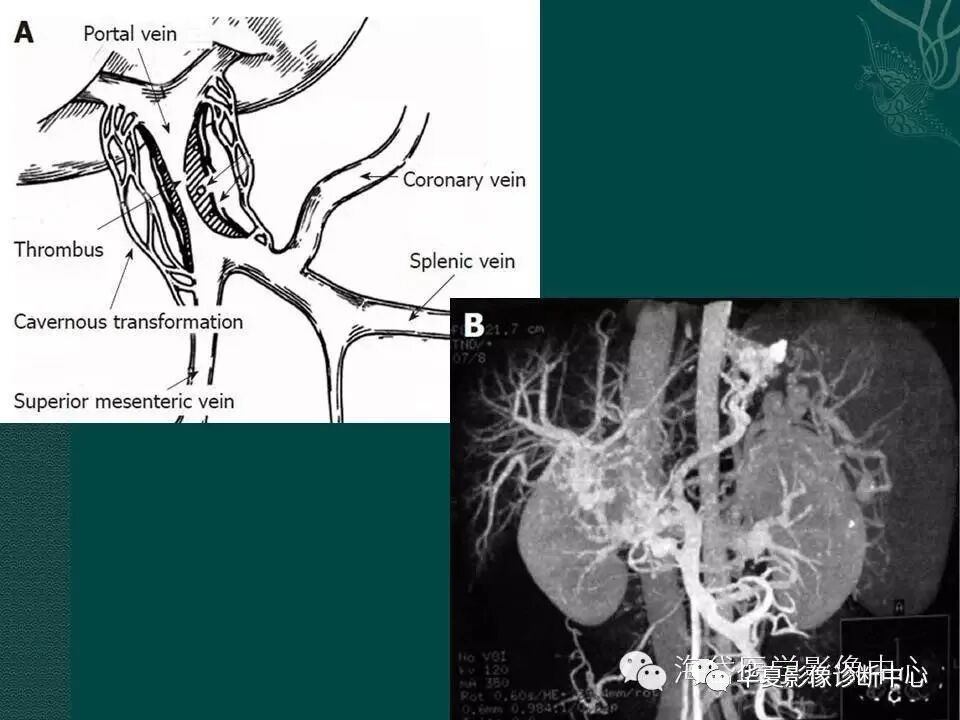

图3 门静脉血栓形成

图5 门静脉主干狭窄闭塞伴侧枝循环

图6 门静脉主干狭窄闭塞伴侧枝循环,脾肾静脉交通胆囊静脉增粗形成假肿瘤征